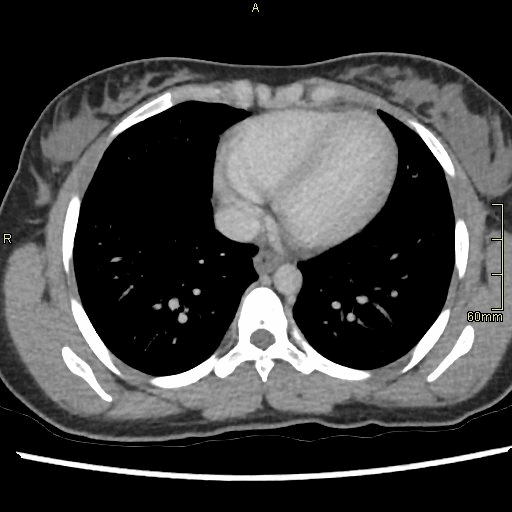

CTPA (Axial)

Portal Venous Abdomen (Axial)